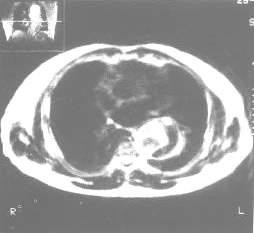

輔助檢查

張平胸部X線檢查:胸部X線檢查是簡便可靠的診斷方法。夾層主動脈動脈瘤累及升主動脈的病例,在胸部X線平片上顯示縱隔陰影向右側增寬,累及降主動脈者則向左側增寬。主動脈弓呈局限性隆起,升主動脈與降主動脈外徑懸殊,升主動脈與主動脈弓擴大、變形。主動脈壁增厚,致內膜鈣化斑與主動脈外緣間距增寬。間隔半小時重複攝片,顯示胸主動脈與縱隔形態發生改變。有時主動脈呈現雙腔陰影。有的病例可顯示胸膜腔積液。胸部X線檢查顯示上述異常者應立即作主動脈造影檢查,要求充分顯示主動脈全長(從主動脈瓣到腹主動脈分叉處)。主動脈造影可顯示主動脈壁剝離形成的血流異常通道壓迫主動脈腔,了解主動脈壁剝離段的長度、內膜裂破的部位、主動脈瓣的解剖及功能情況以及主動脈主要分支如頸總動脈、腎動脈受累情況等。夾層動脈瘤的主動脈造影陽性徵象有:造影劑在主動脈內分為兩個通道且形態不光整,造影劑未能進入主動脈主要分支以及主動脈瓣關閉不全。